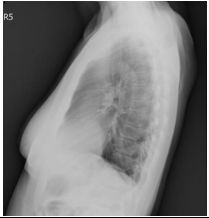

1. A 39-year-old man had this chest X-ray on his health exam. No any clinical symptoms.